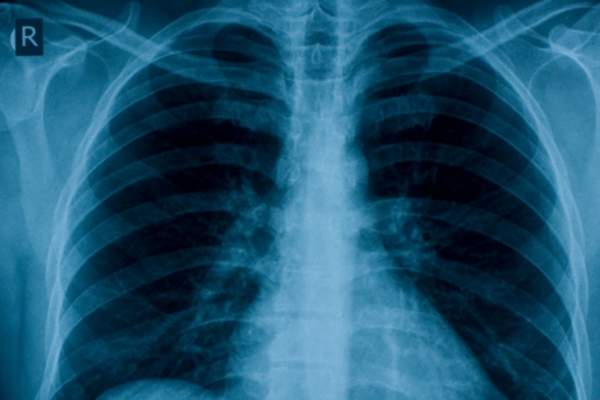

对于患有慢性阻塞性肺病和其他相关呼吸系统疾病的人来说,这些提示可以帮助他们避免突发疾病。

来自圣路易斯华盛顿大学医学院研究发现,某些综合环境因素,如污染和吸烟,可以触发白细胞介素-13 (IL-13)分子,引起免疫反应,产生在COPD和其他呼吸系统疾病中常见的过量黏液。